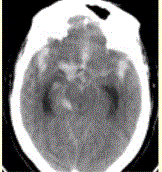

患者男,50岁,突发昏迷、呕吐1h。查体:颈项强直,脑膜刺激征阳性,CT表现如图1。CTA结果如图2所示,该患者的诊断为(左右与人体一致)...

问题 患者男,50岁,突发昏迷、呕吐1h。查体:颈项强直,脑膜刺激征阳性,CT表现如图1。 CTA结果如图2所示,该患者的诊断为 (左右与人体一致)

选项 A.动静脉畸形 B.海绵状血管瘤 C.发育性静脉畸形 D.烟雾病 E.基底动脉尖和右侧颈内动脉末端动脉瘤

答案 E